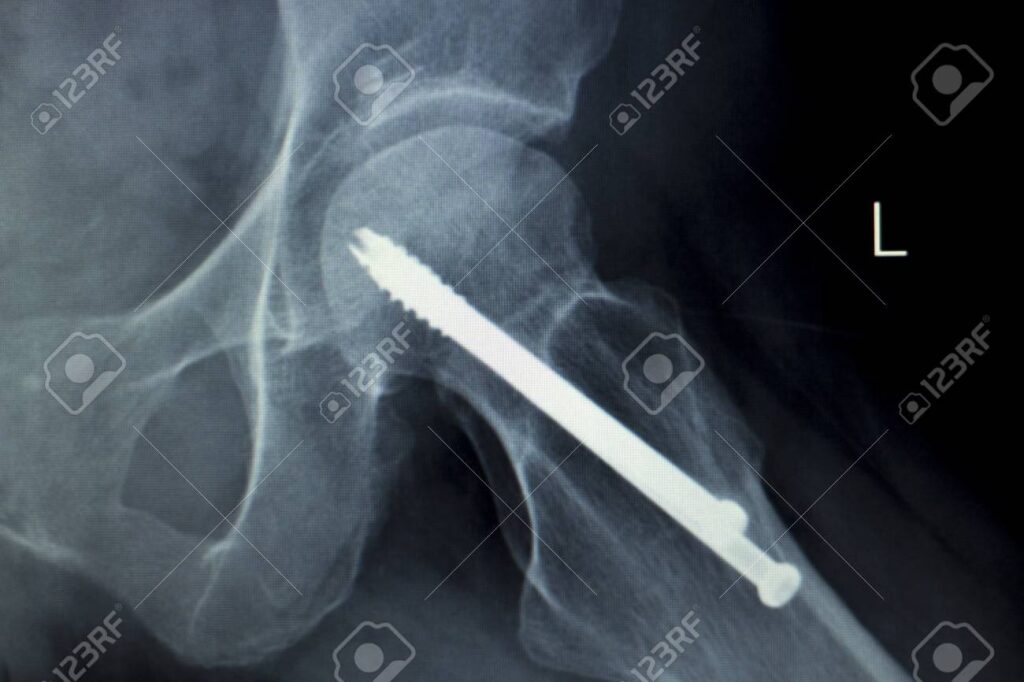

- Placas Óseas para Reparación de Fracturas: Utilizadas ampliamente para tratar fracturas mediante reducción anatómica, estas placas, junto con tornillos, alambres y clavos, mantienen unidos los fragmentos óseos. Su objetivo es restaurar las funciones del tejido óseo, permitiendo la curación y la recuperación del movimiento. Los metales como el acero inoxidable, las aleaciones de Co-Cr o el titanio son los materiales de elección por su resistencia y durabilidad.